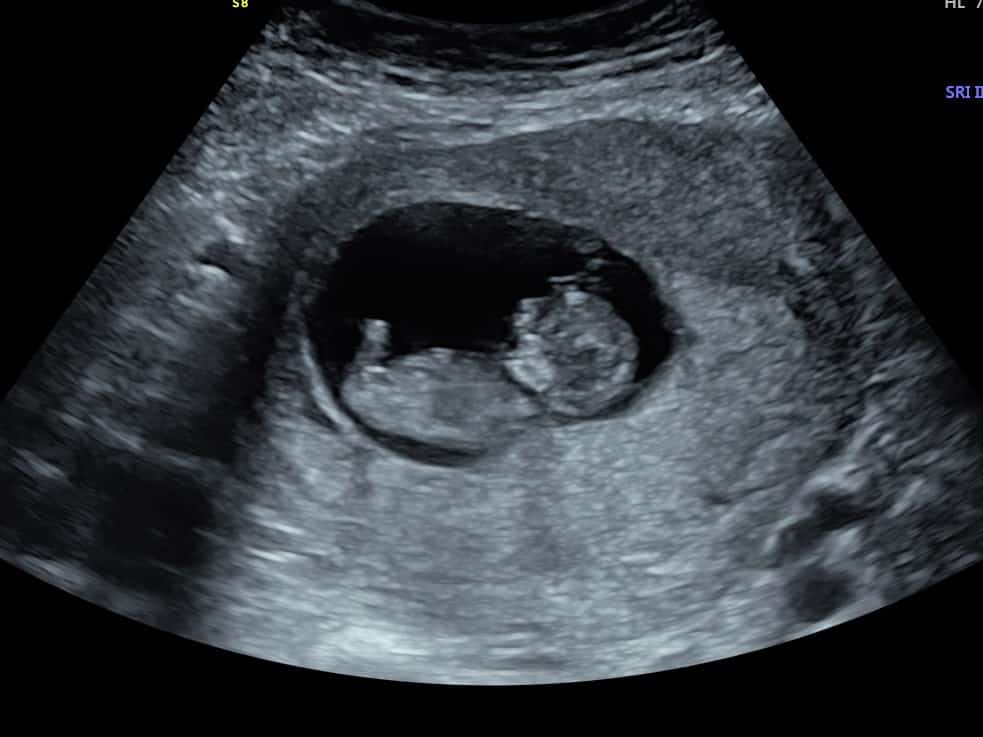

At 6 weeks, baby is only around 4mm so is very small. You’ll see a pregnancy sac, a yolk sac (which provides baby with all the nutrients they need until the placenta takes over, around week 10) and baby’s heartbeat.

We will either base it on your LMP (last menstrual period). If you’re unsure of your dates, we can still offer you a scan; we will book you in from 2 weeks after your first positive pregnancy test. This ensures you’re at least 6 weeks. If you’re feeling very anxious, we would recommend trying to wait until nearer the 7 week mark. This is just incase there’s a slight discrepancy with your dates. Baby has doubled in size to 8mm by week 7, so you may leave us feeling more reassured than at 6 weeks, due to how clear we can see baby.

The first thing the sonographer looks for is the position of baby. They will check the baby is in the uterus as it should be, rather than elsewhere which can be dangerous for mum. The sonographer will then look for the number of pregnancy sacs and babies to confirm a single or multiple pregnancy. The heartbeat is next; during your early pregnancy scan we do not listen to the heartbeat as it wouldn’t be safe for baby, but we will show you the heartbeat flickering on our screens.

Once the pelvic assessment is complete, the sonographer will return to your baby and measure their length from crown to rump (head to tail) to provide you with accurate dating.